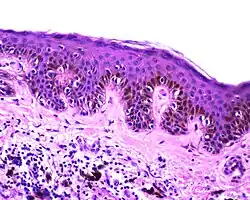

| Junctional nevus | Along the junction of the epidermis and the underlying dermis.[15] | May be colored and slightly raised.[16] |

ICD10: D22 ICDO: M8740/0 |